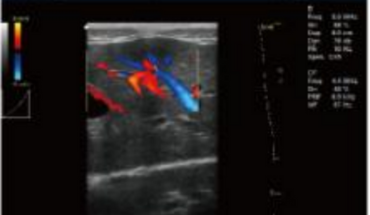

- B+CF (Dual Images)

- B+CF/DPDI+PW (Triplex)